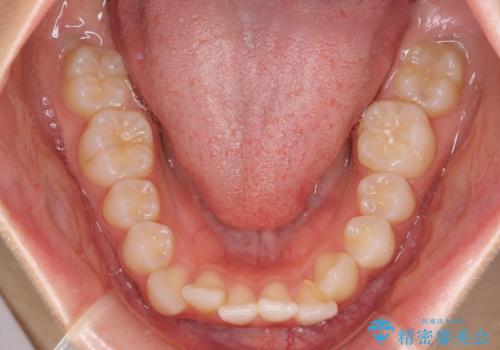

- 前歯のデコボコとクロスバイトを気にして来院された患者様です。

上顎側切歯(上の真ん中から2番目の歯)が舌側転位している場合、インビザラインでは仕上げきれないことが多く、更には無理して動かそうとすると歯髄壊死を起こすリスクが高いと言われています。

今回は、ワイヤー装置を併用することなく、インビザライン単体で矯正治療を行うこととしました。